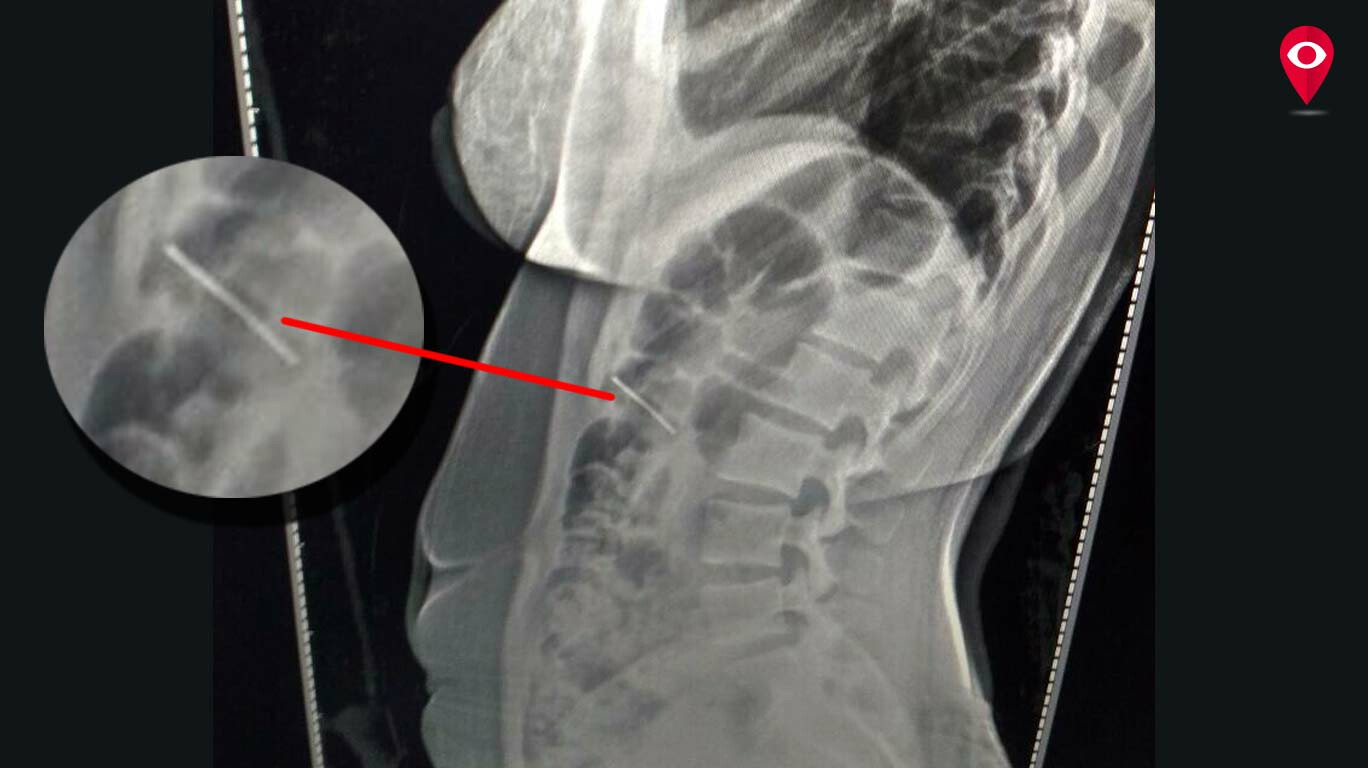

Woman swallows needle while sewing

From www.mumbailive.com

Woman swallows needle while sewing What To Do If You Swallow A Sewing Needle if you or someone you know has swallowed a sewing needle, it’s natural to feel a surge of panic. A healthcare professional will be able to assess the situation and determine the best course of action. The needle can be swallowed or worse get stuck in the back of throat or aspirate into the lungs. The first thing you. What To Do If You Swallow A Sewing Needle.